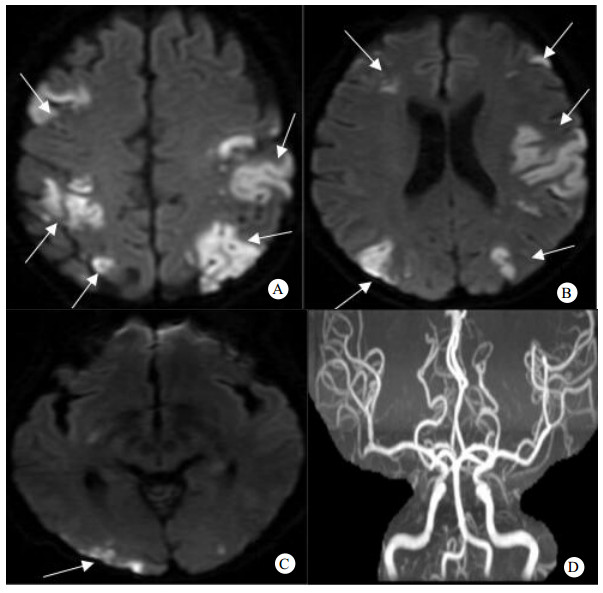

2.2 临床表现、实验室及影像学检查9例患者的症状表现:肢体无力6例、言语不利6例、意识障碍5例、癫痫2例、头晕1例。TS评分4(4, 5); 纤维蛋白降解产物水平12.8(4.9, 70.2)μg/mL(正常参考值0~5),D-二聚体水平(5.4±4.8)mg/L(正常参考值0~0.55),血脂均正常,肿瘤类型均为实体肿瘤,其中胃癌3例,肺癌2例,卵巢癌3例,宫颈癌1例; 病理类型腺癌7例,鳞癌2例; 肿瘤转移部位有淋巴结4例、腹膜4例、肺3例、肝2例、骨2例、肾上腺1例、皮肤1例。发生1次脑梗死者4例,2次脑梗死者3例,3次脑梗死者2例。脑梗死部位分布于双侧前和双侧后循环者6例,分布于单侧前和双侧后循环者2例,分布于双侧前和单侧后循环者1例。其中病例1头颅影像见图 1。6例患者出现了外周静脉血栓形成,其中1例患者四肢深静脉均有血栓形成且同时存在肺栓塞、肾梗死及脾梗死,余5例患者为双下肢深静脉血栓形成,见表 1、表 2。

| A、B、C:DWI(磁共振扩散加权成像) 示双侧额顶叶、左侧颞岛叶、右侧基底节区、右侧颞叶、双侧枕叶、右侧小脑半球多发片状高信号病灶;D:脑MRA(磁共振血管成像)无明显异常 图 1 病例1头颅DWI及MRA结果 |